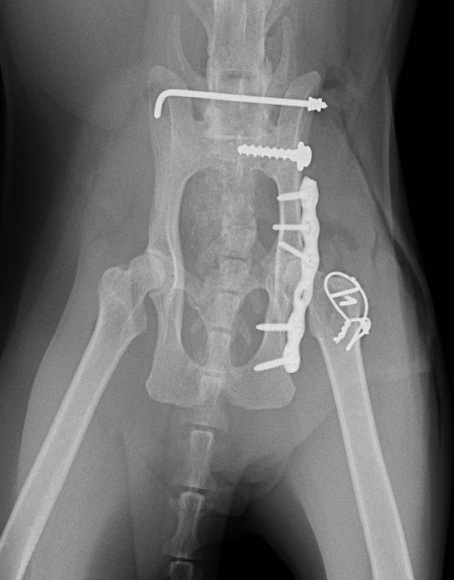

レントゲン検査で、左側の仙腸関節離断と同側の寛骨臼の骨折をしていることがわかりました。 寛骨臼の骨折は坐骨からの斜骨折を伴うもので、人の下顎骨骨折に用いられるMatrix Mandibleというプレートで整復しました。

高齢でしたが術後経過は良好で、椅子にも飛び上がれるようになりました。

腹背像

レントゲン検査で、左側の仙腸関節離断と同側の寛骨臼の骨折をしていることがわかりました。 寛骨臼の骨折は坐骨からの斜骨折を伴うもので、人の下顎骨骨折に用いられるMatrix Mandibleというプレートで整復しました。

高齢でしたが術後経過は良好で、椅子にも飛び上がれるようになりました。

腹背像